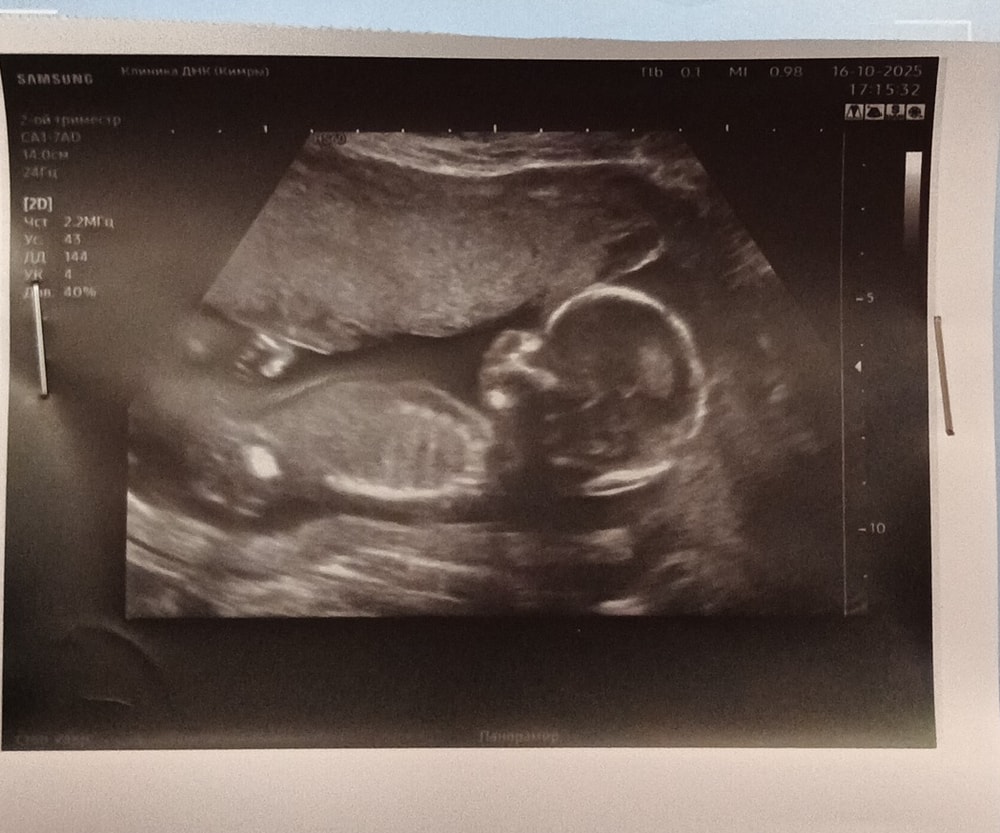

Девчонки, пропала что-то я, давно не заходила. А все потому что очень переболели с мужем. Врачи говорят была какая то корона только кишечная. Переболели 3 недели и вот по тихоньку идем на поправку. Но суть не в этом, сегодня были на узи, а точнее, на втором скрининге

до сих пор не понимаю как считать срок, ведь у меня очень короткий цикл (21-24 дня)